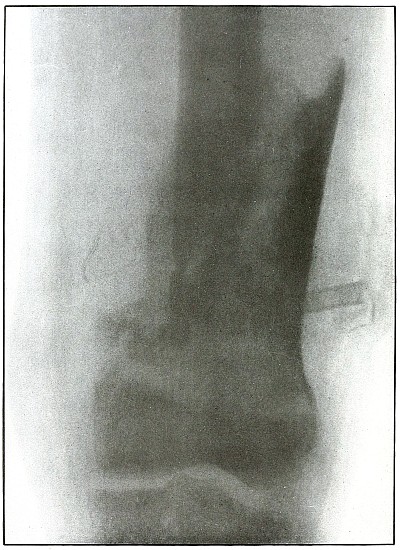

| 72. |

Gunshot fracture, ankle |

154 |